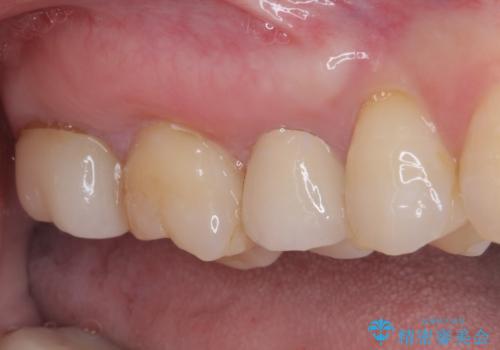

- 見た目の不揃いなセラミックと、痛みを感じる歯を気にして来院された患者様です。

右上の歯は噛んだときに何カ所か痛みを感じるとのことで、診査したところ第二小臼歯が患歯と疑われました。

患者様は他の歯にも痛みを感じるとおっしゃっていましたが、そのような所見が認められなかったため、まずは第二小臼歯を処置し、その痛みが引いた後に再診査することとしました。

痛みが引いた後、不揃いな見た目で気になっていた左下の奥歯とともにオールセラミッククラウンにて補綴治療を行うこととしました。

右上の歯は、第二小臼歯の初回処置後に痛みを感じなくなったため、他の歯については問題なしと診断しました。

将来ホワイトニングをされるとのことで、前歯よりもやや白い色合いのオールセラミッククラウンを選択されました。